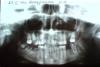

Aldo Rain Опубликовано 21 августа, 2010 Поделиться Опубликовано 21 августа, 2010 Всем доброго времени суток. г. Орел. Хотелось бы получить консультацию профессионалов.Был перелом нижней челюсти справа. В стационар лег на 5-й день (пока понял, что что-то не так, пока рентген, бумаги, работа...). Сразу поставили шины (самогнутые). В стационаре находился 7 дней. 3 раза в день антибиотики. потом выписали и направили обследоваться к своему стоматологу. (Кстати в больницу пошел потому, что изменился прикус, очень плохо открывался рот и больно было что-то кусать). Отходил по-полной с шинами (ещё 20 дней), раз в неделю показываясь к стоматологу. Это всё хорошо. Стоматолог был мужчина, вполне серьезный и внушал надежду. Когда пришел снимать шины, этого мужчины не оказалось (в отпуске), а шины мне снимала женщина, которая их видимо вообще в первый раз видит (она вечно говорила "как хоть они.." и неумело тыкала то пинцетом, то ножницами, а я ей подсказывал, что делать). В результате я не получил ни одной рекомендации как при выписке из больницы, так и при снятии шин и окончательной выписке. А рот как не открывался по-человечески, так и не открывается (открывается так, что ровно сосиска пролезает), и зубы передние поискривились и болят теперь вместе с деснами, и как-то повылезли из десен. Прикус остался немного изменен, небольшая опухоль осталась и небольшой бугорок в месте перелома.Я тут почитал эту ветку форума... Как видно вариантов есть очень много разных с разными последствиями. Хотелось бы получить рекомендации о том, что делать дальше. Как разрабатывать челюсть (или не надо)?Что можно, что нельзя (еда твердая, мягкая) и в какие примерно сроки что должно произойти? (спадет опухоль, восстановится или не восстановится прикус, что будет с передними зубами). Спасибо за ранее за ответы.Мы тут вам насоветуем,а может у вас перелом не сросся,нужны снимки нчел в прямой проекции и ортопантомограмма. Лучше сходить к знающему спецу на осмотр. Ссылка на комментарий

slgraf Опубликовано 22 августа, 2010 Поделиться Опубликовано 22 августа, 2010 Мы тут вам насоветуем,а может у вас перелом не сросся,нужны снимки нчел в прямой проекции и ортопантомограмма. Лучше сходить к знающему спецу на осмотр. Дело в том, что не знаю куда ещё обратится. Такое ощущение, что врачи ничего не знают... никто не сказал мне ничего конкретного. А можно по-подробнее, что надо выложить и где делают эти снимки? Ссылка на комментарий

Doc Опубликовано 24 ноября, 2010 Поделиться Опубликовано 24 ноября, 2010 Здравствуйте! Суть: сестра 36 лет с диагнозом - открытый ангулярный перелом нижней челюсти справа, острый посттравматический остеомиелит поставлен в ММАУ Стоматологическая п-ка№1 СПУСТЯ 20 дней после травмы!!! Я в шоке, врачи видимо тоже, прописали антибиотики и ожидание. Может есть другие варианты?HELP!!! Уточните данные, пожалуйста! Ничего же непонятно. Открытый перелом диагностировали только через 20 дней??? Или через 20 дней остеомиелит развился??? Зубы удалялись или все так, как сейчас на снимке? В общем, хоть какую-то конкретику дайте врачам, чтобы могли понять что там происходит и примерно сказать что с этим делать. Напишите пожалуйста, как называется метод которым Вас лечили? Подозреваю, что остеосинтез. Ссылка на комментарий